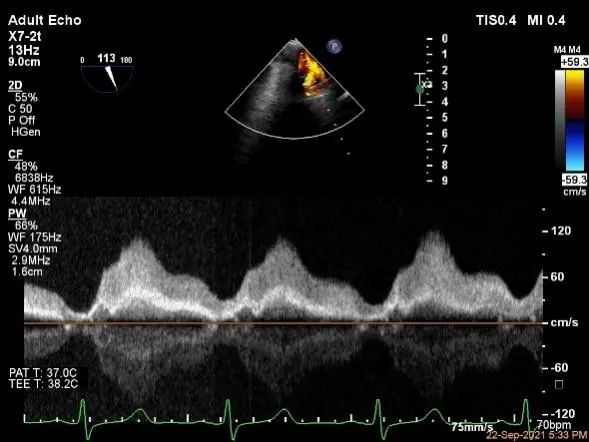

术中超声

3D:P1区脱垂并腱索断裂,Width:11.4mm

3D-color:重度MR,4级

麻醉状态下肺静脉血流频谱

MVA:7.8cm²,平均跨瓣压差:1mmHg

肺静脉血流频谱恢复正常